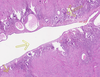

4

Q

Name of the Detail:_____?

A

Cystically Dilated Gland

7

Q

Name of the TWO Details: _____?____?

A

Stroma — Stromal Fibrosis